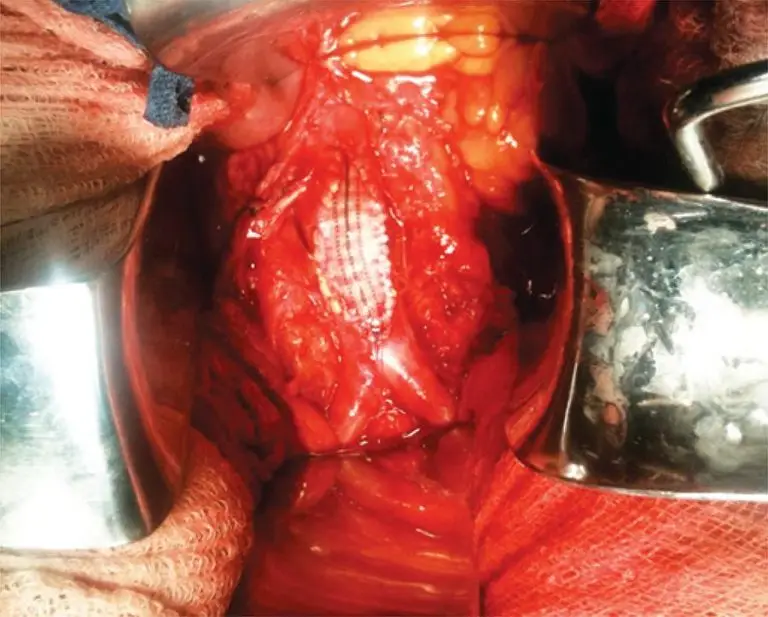

Coral reef aorta is described as an uncommon entity characterized by the presence of coarse calcifications, which are developed in the visceral aorta. These calcifications grow toward the lumen of the artery and can result in significant stenosis, so that causing malperfusion of the lower limbs, visceral ischemia or hypertension secondary to renal involvement. We report here a case of a 54-year-old patient with coral reef aorta and symptomatic. The clinical presentation of the patient required the surgical approach. A […]

Keywords: Aorta; Aorta, abdominal; Atherosclerosis; Case reports; Emergencies; Endarterectomy; Ischemia